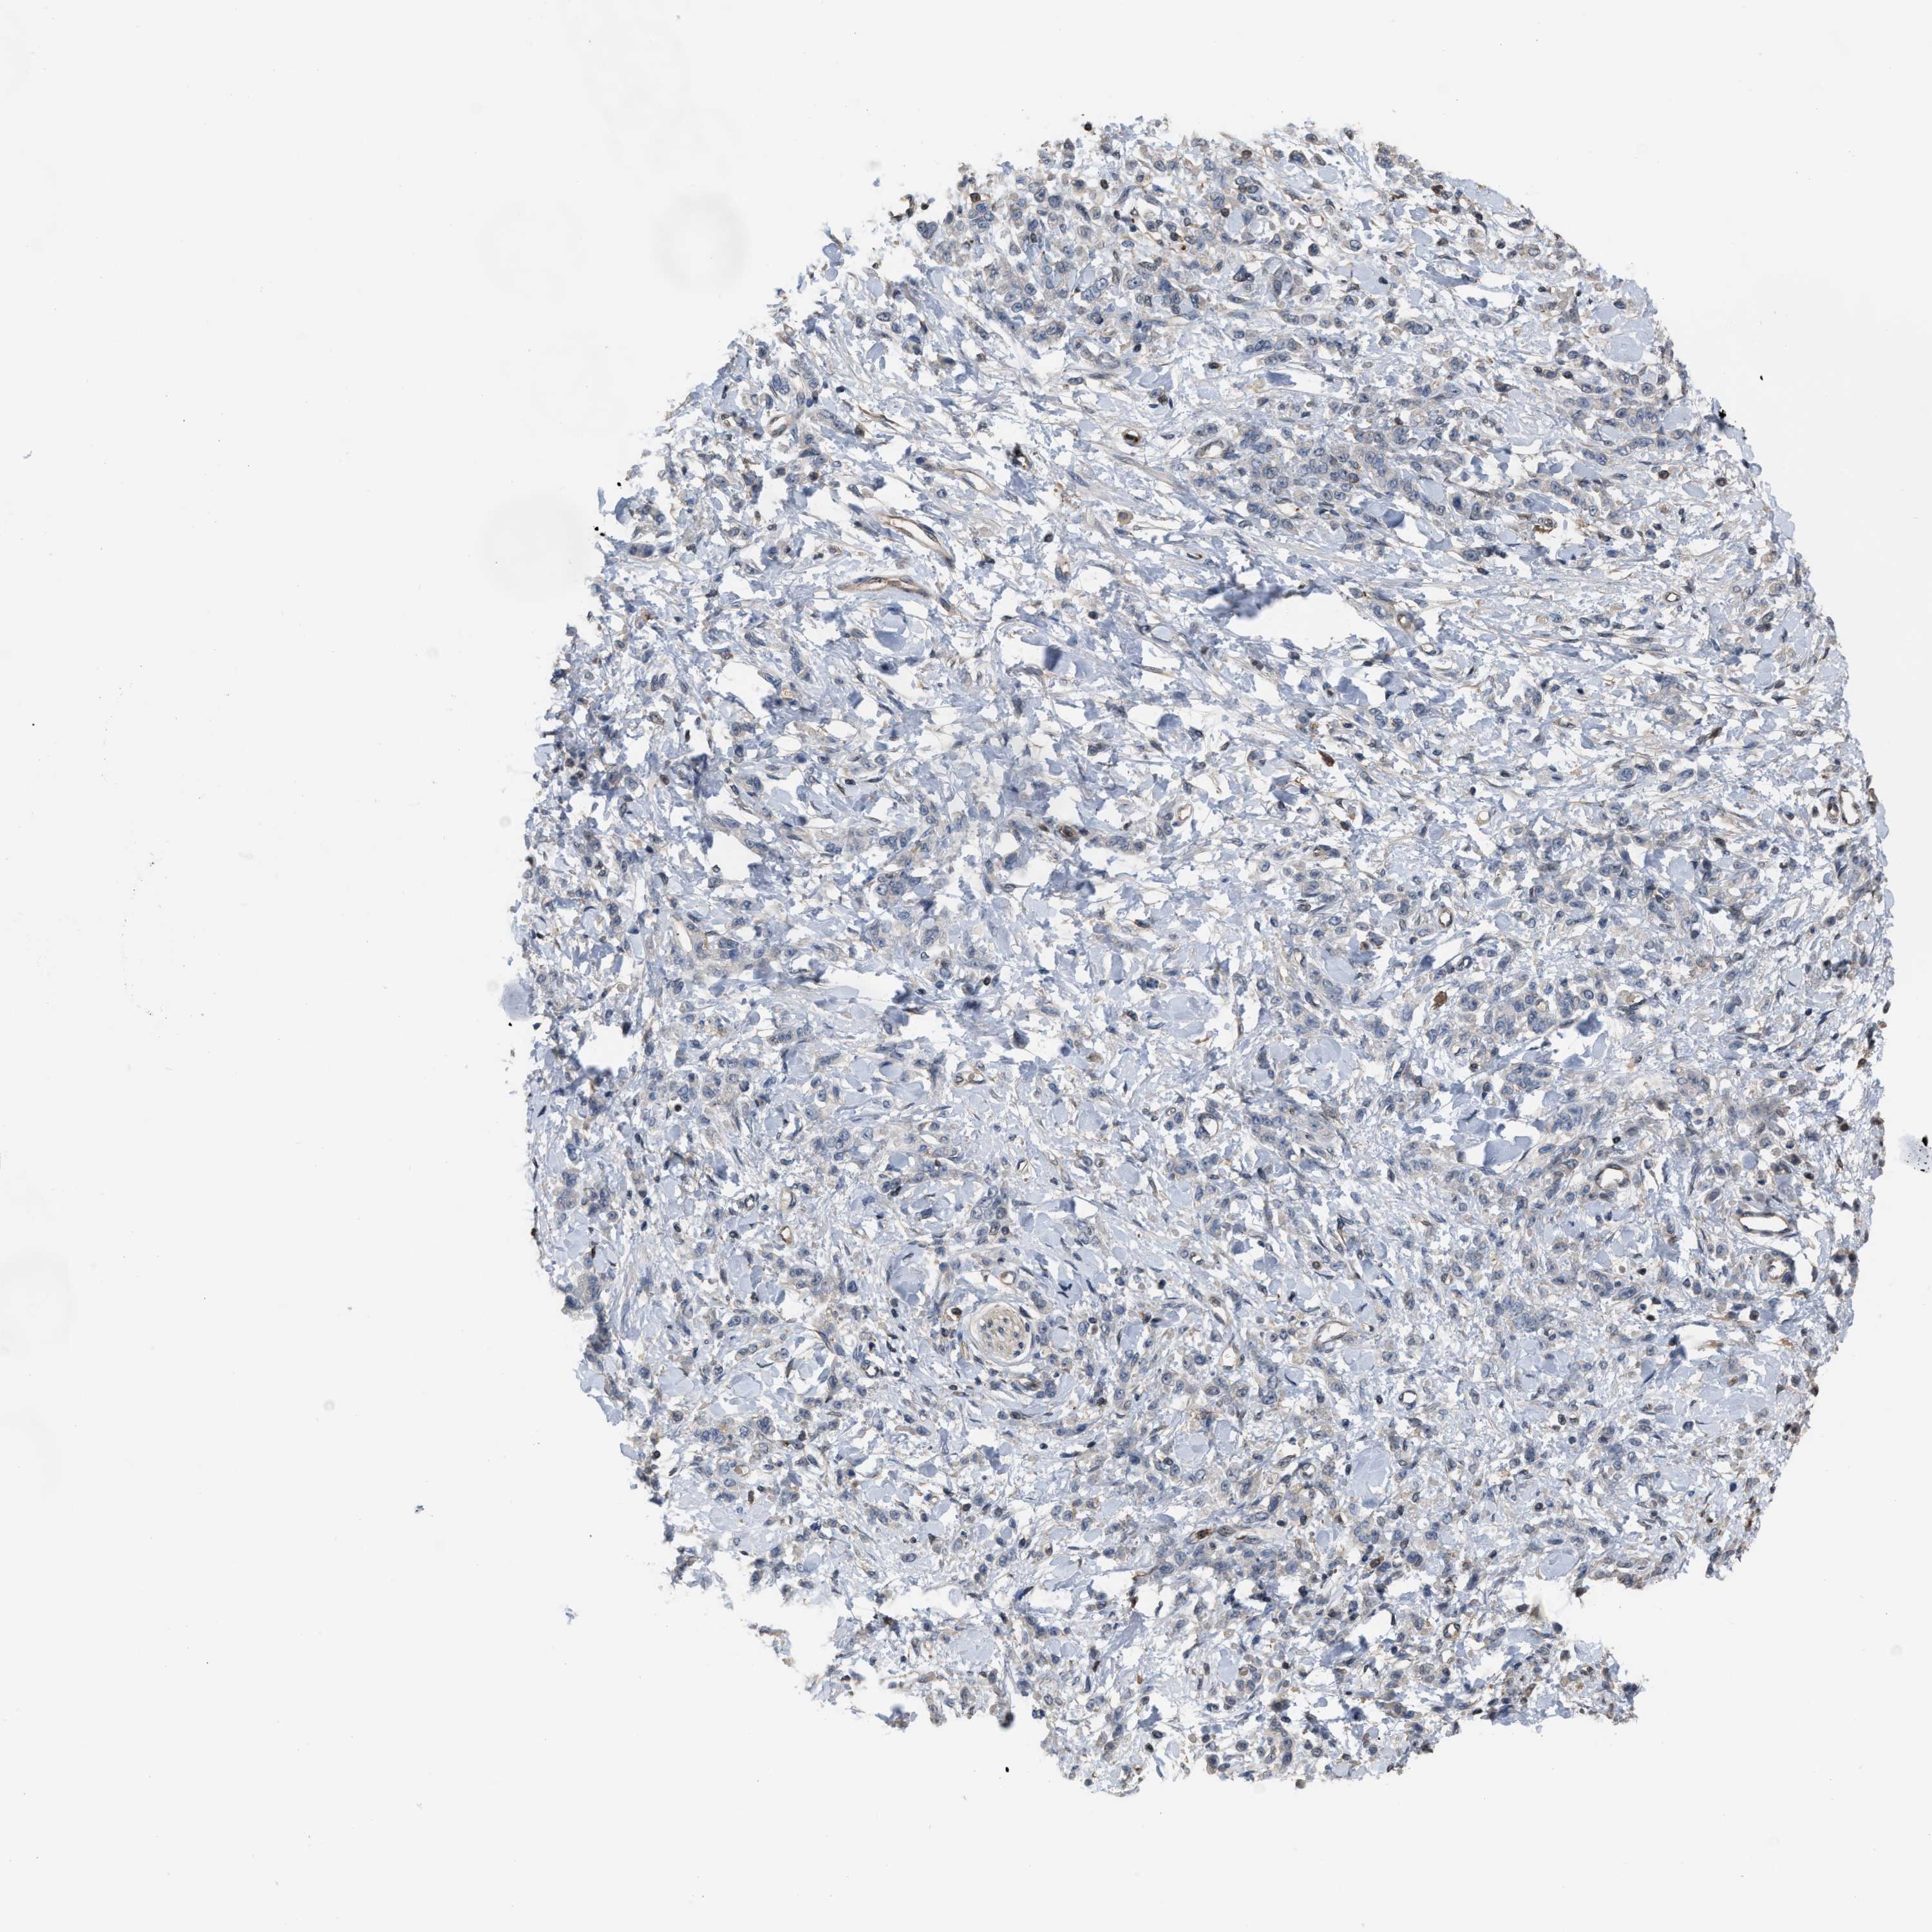

STOMACH CANCER - Protein expressioni

A mouse-over function shows sample information and annotation data. Click on an image to view it in a full screen mode. Samples can be filtered based on level of antibody staining by selecting one or several of the following categories: high, medium, low and not detected. The assay and annotation is described here.

Antibody stainingi

Antibody staining in the annotated cell types in the current human tissue is reported as not detected, low, medium, or high, based on conventional immunohistochemistry profiling in selected tissues. This score is based on the combination of the staining intensity and fraction of stained cells.

Each image is clickable and will lead to virtual microscopy that enables deeper exploration of all samples and also displays staining intensity scores, fraction scores and subcellular localization as well as patient and tissue information for each sample.

Antibody HPA019735

Staining

High

Medium

Low

Not detected

Intensity

Strong

Moderate

Weak

Negative

Quantity

>75%

75%-25%

<25%

None

Location

Nuclear

Cytoplasmic/membranous

Cytoplasmic/membranous,nuclear

Adenocarcinoma, NOS